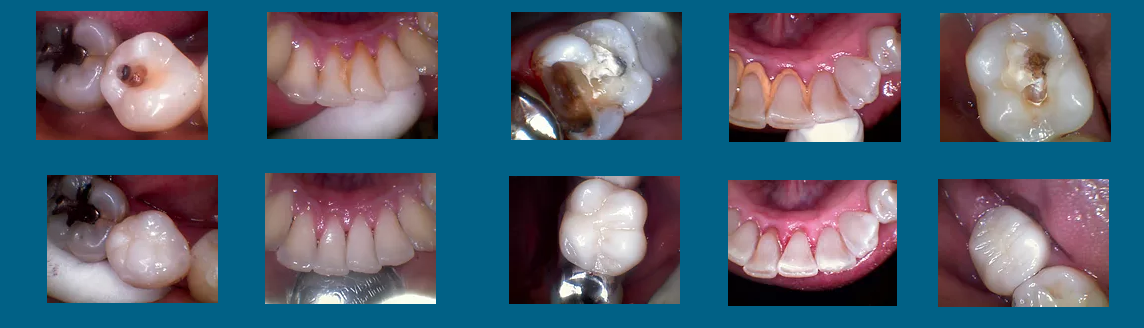

Nuestro objetivo principal es la calidad en nuestros tratamientos por lo cual te ofrecemos una consulta en la cual se te dará el tiempo suficiente para que el procedimiento tenga el mejor resultado. Nuestros tratamientos llevan un registro radiológico y fotográfico para que puedas observar el cambio en una foto de antes y después para lograr la satisfacción de nuestros pacientes.